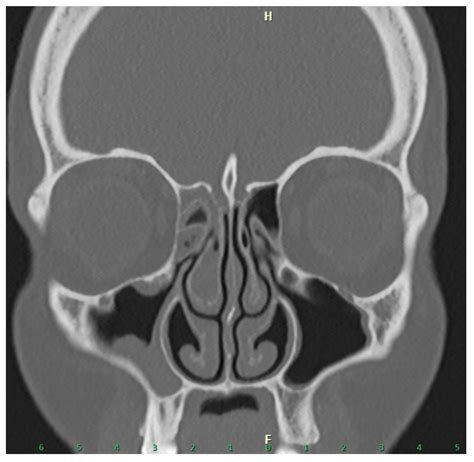

The sinuses are hollow, air-filled cavities within the skull that are lined with mucous membranes. When these membranes become inflamed or the drainage pathways become blocked, infection and fluid buildup occur. While many cases resolve with medication, chronic conditions—lasting more than 12 weeks—often require structural correction. The goal of any sinus procedure is to restore natural drainage and widen the openings of the sinuses, allowing them to function properly again.

Modern medical technology has shifted the landscape of sinus care, moving away from invasive external incisions toward minimally invasive endoscopic techniques. Here are the most prevalent procedures performed by otolaryngologists today:

Advancements such as Image-Guided Surgery have revolutionized how surgeons navigate the complex anatomy of the skull. By utilizing real-time CT scan data during the procedure, surgeons can map the surgical field with extreme precision. This technology is particularly beneficial for revision surgeries or cases where the natural landmarks of the sinuses are obscured by severe disease. This high level of accuracy minimizes the risk of complications and ensures that only the necessary tissue is removed, preserving as much healthy anatomy as possible.